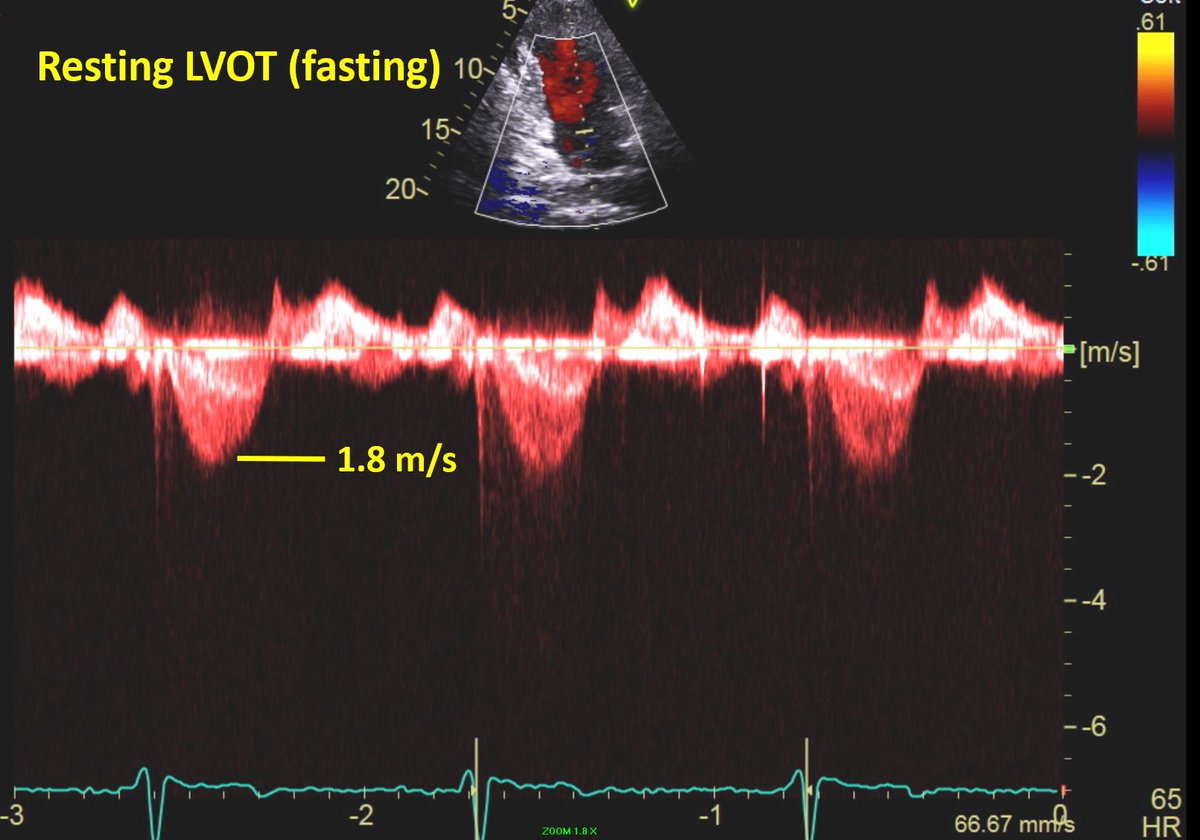

Recent case of a middle aged pt with HCM Echo performed late morning demonstrated no LVOT obstruction (fasting). Patient returned for consultation following lunch & was noted to have loud, harsh 4/6 SEM. Doppler study was repeated which demonstrated severe LVOT obstruction!

Patient concurrently developed severe MR with high velocity jet. This case illustrates the severe hemodynamic effects of eating in some HCM patients with dynamic LVOT obstruction.